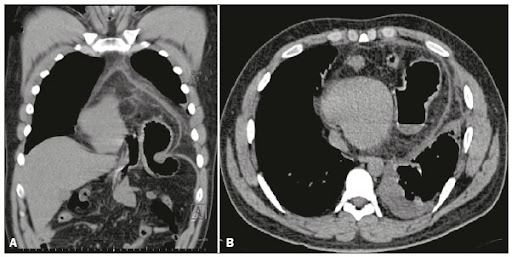

CIR - diagnóstico e conduta

hérnia diafragmática - lapa, exploração cavidade, redução do conteúdo